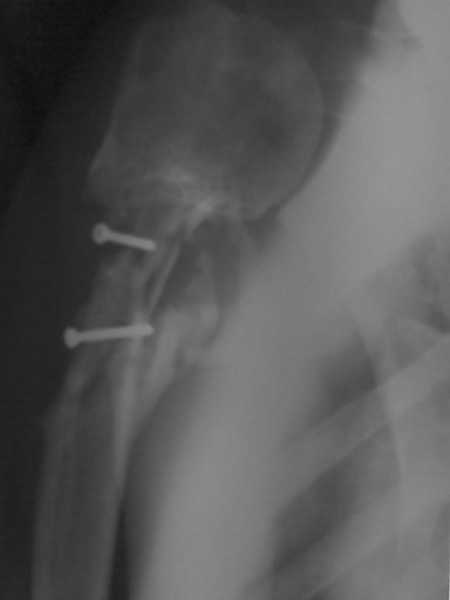

Более года назад пациент был оперирован в одном из НИИТО. При контрольном осмотре через год: болевой синдром, контрактура в локтевом суставе, патолгическая подвижность нижней трети плеча

Неудачный остеосинтез пластиной: поломка винтов, миграция фиксатора. После удаления пластины сформировался гипопластический ложный сустав нижней трети бедренной кости, укорочение н/к 5 см. Выполнялся дистакционный остеосинтез аппратом Илизарова на штифте. Зона ложного сустава "не открывалась". Через 10 месяцев, когда даже регенерат полностью перестроился, консолидации в зоне ложного сустава не наступило, несмотря на стабильную фиксацию и постоянную компрессию(штифт+аппрата на 4 кольцах).